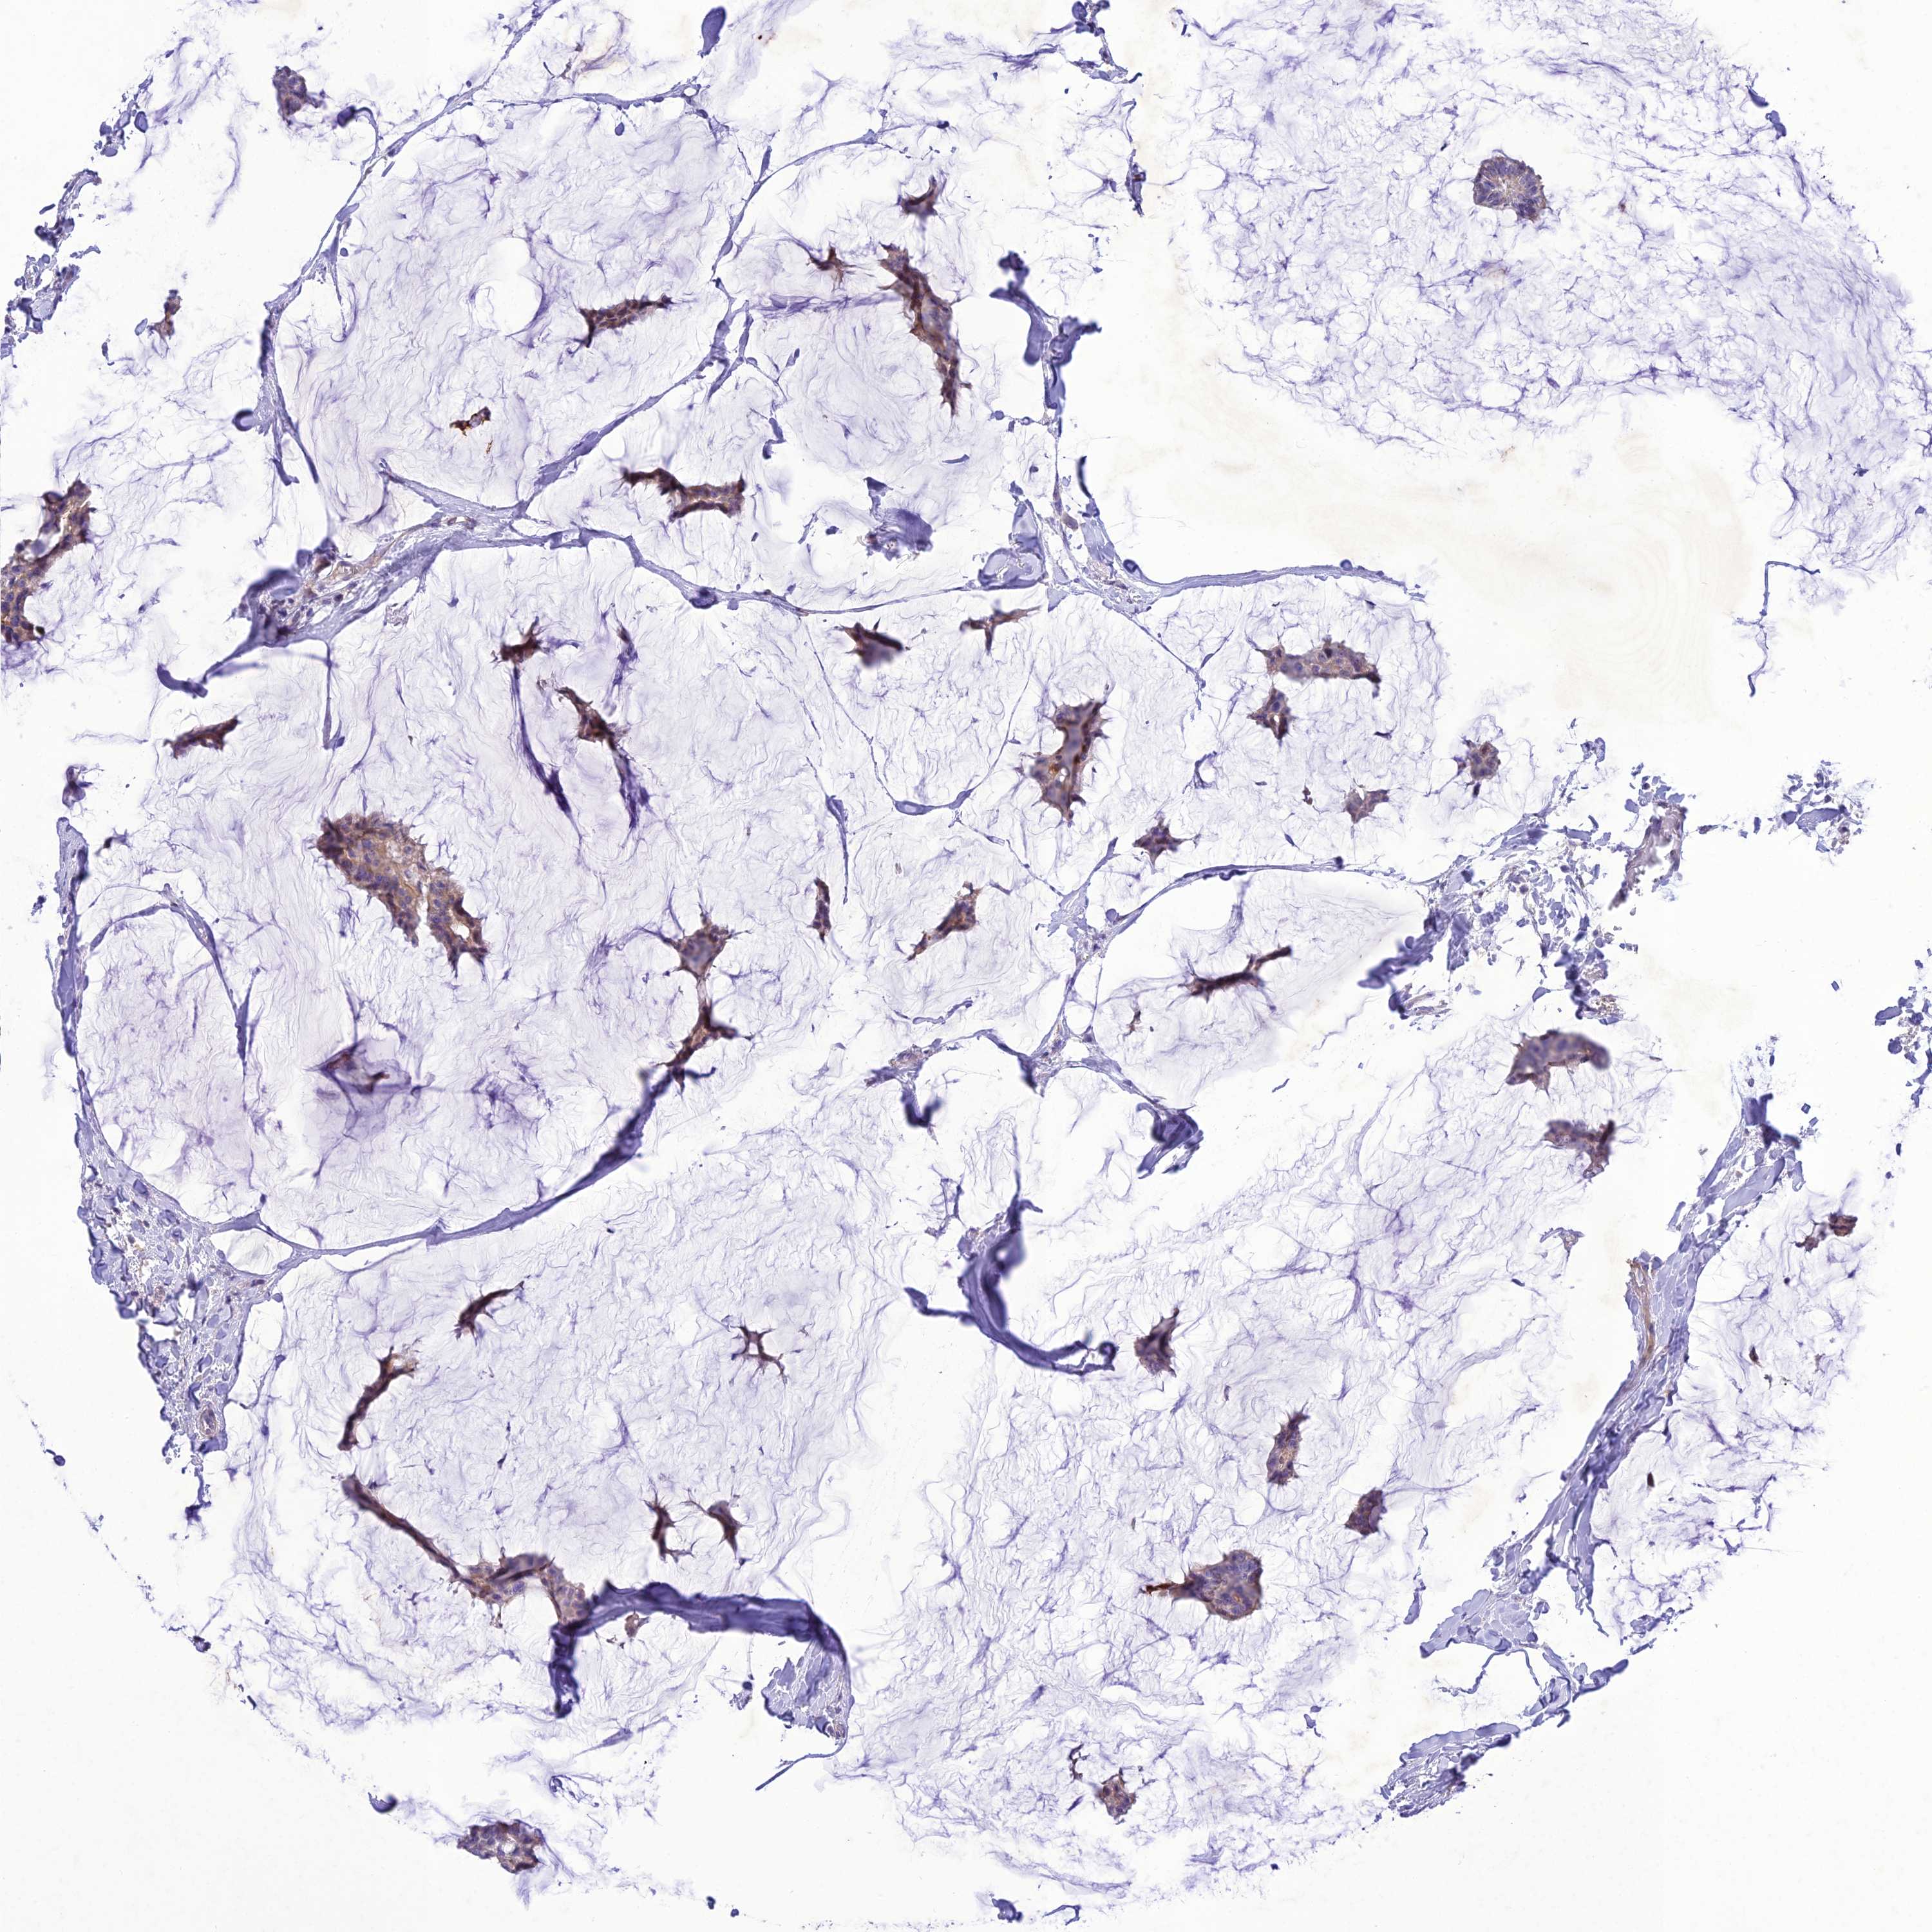

CANCER BREAST CANCER Show tissue menu

BRCA TCGA BRCA VALIDATION PROTEIN EXPRESSION